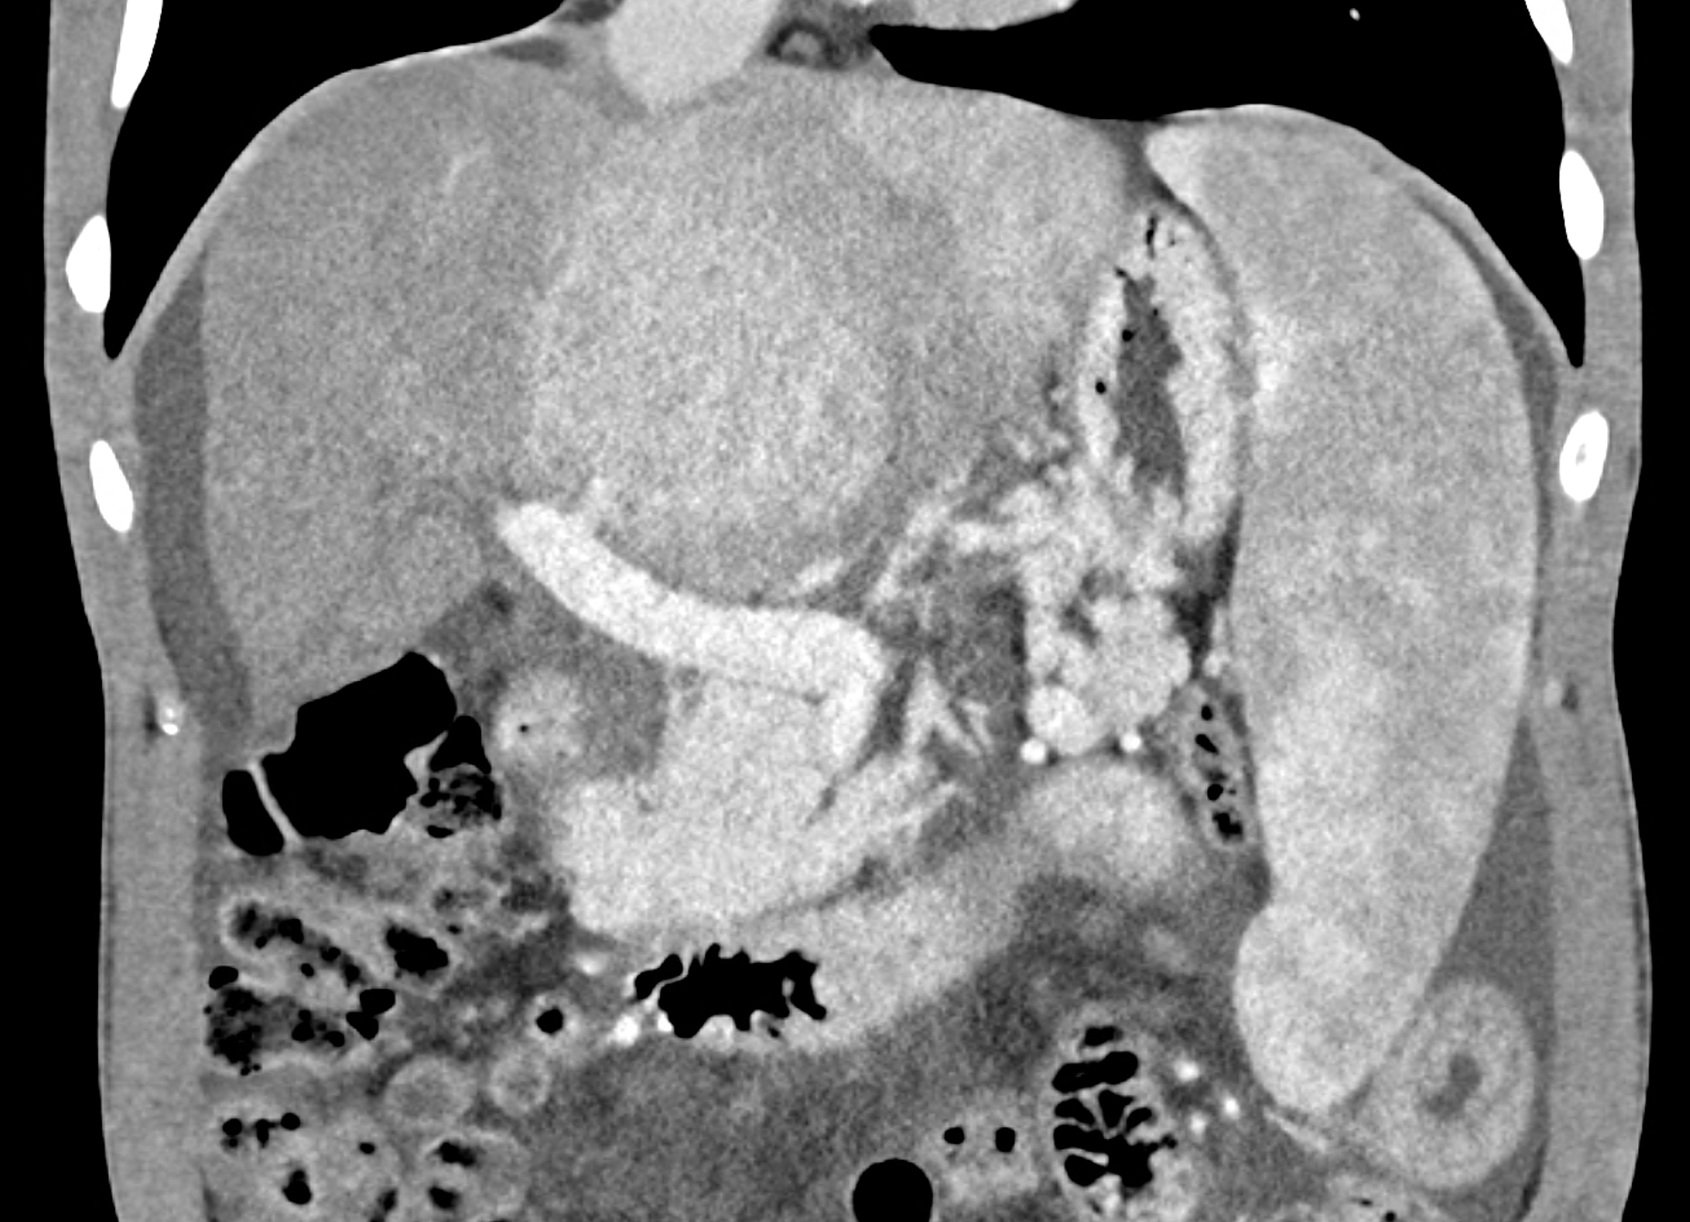

In CT images, BCS manifests as non-homogeneous enhancement of liver tissue in the arterial and especially in the portal phase, although in the portal phase may be increased, especially in the caudate lobe and left lobe, which are often hypertrophic (the hypertrophy and the enhancement is caused due to the possibility of the venous drainage directly into the inferior vena cava through the direct caudate veins), in contrast to the reduction in the right lobe. The portal vein is free, whereas even in the late phase, the hepatic veins and their contrast filling are not visible. Thrombotic occluded veins are hypodense.

A patient in his sixties with a Leiden mutation of factor V and a heterozygous prothrombin mutation presents with abdominal pain. Ultrasound examination reveals ascites and enlargement of the liver.There is enlargement of the liver, particularly the left lobe and caudate lobe. The hepatic veins are centrally filled with contrast medium due to reflux at the confluence with the inferior vena cava, and their radicular parts are thrombosed. There is typical chronic liver remodelling and the formation of centrifugal collateral circulation, including esophageal varices, and ascites is present in the abdominal cavity.

coronary view documenting splenomegaly, different enhancement of the liver parenchyma, and ascites, the arterial, and the portal phases